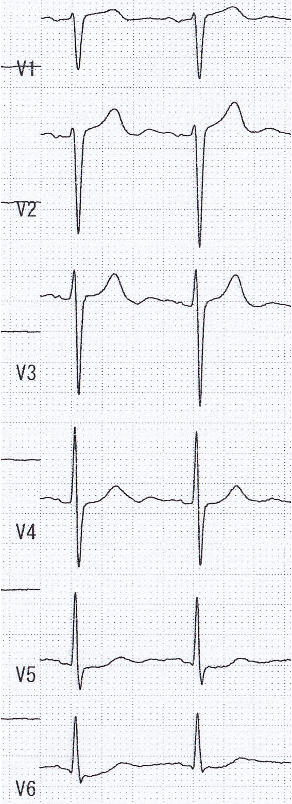

RCA: Seg1)total occlusion, Bypass graft SVG-RCA 99%. LCA:LAD Seg7)total occlusion,LCx Seg12)90%,seg13)90%.seg14)total occlusion, Bypass graft LITA-LAD・FreeRITA-LCX patent, SVG-seg9)occluded.

PCI for the degenerated SVG was determined to be at high risk of distal embolism so we planned to perform PCI for native RCA. Antegrade wire crossing was thought to be difficult (J-CTO score was 3 : calcification, bending and lesion length), therefore we planned retrograde approach via SVG. To avoid ischemia during the retrograde procedure, we dilated the severe stenotic lesion in SVG with small balloon and then micro catheter was advanced. It was very difficult to pass the graft anastomosis, but reverse wire technique at distal RCA was effective. Even after the advancement of both antegrade and retrograde wires, it was also difficult to pass the CTO lesion due to strong bending. Finally, retrograde wire was passed with Reverse CART technique and externalization was achieved. After DES implantation, native RCA was nicely revascularized.